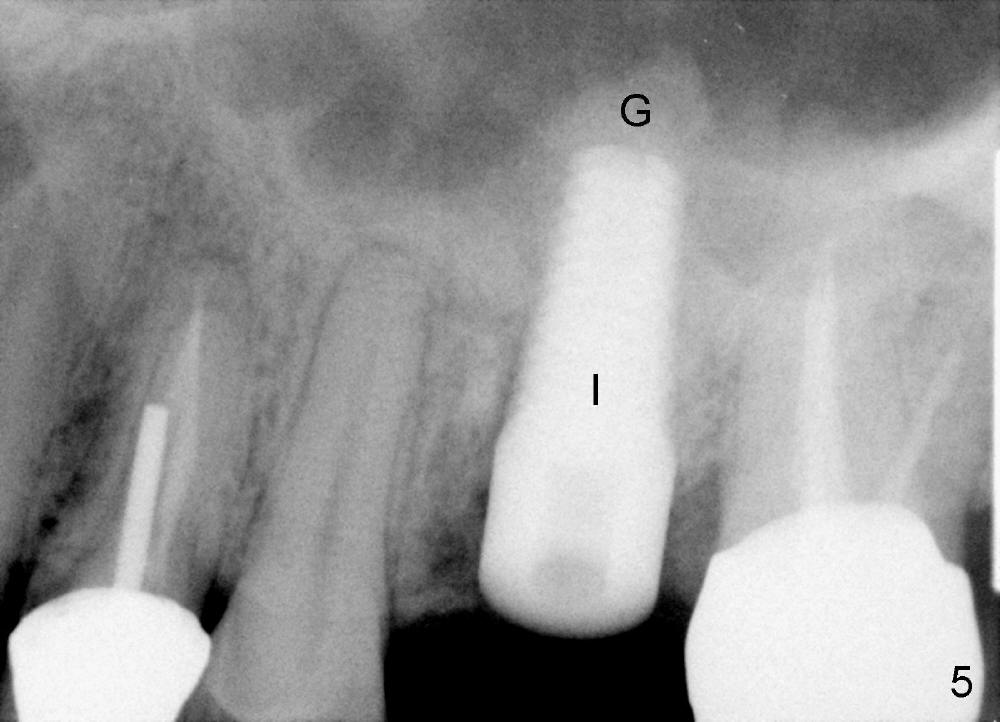

The upper left 1st molar is extracted with sectioning. The septum is large. A surgical fissure bur is used to initiate an osteotomy in the middle of the septum (Fig.1 <; P: palatal socket, MB: mesiobuccal socket), followed by tapping with resistance a 2 mm osteotome ~ 8 mm into the septum. It is tougher to drive 3 mm osteotomy. A 2.5 mm reamer is used to enlarge the osteotomy at 50 RPM at the same depth. Then it is relatively easy to tap 3 and 4 mm osteotomes at ~ 8 mm into the septum. A 4.5x17 mm tap is inserted 8 mm deep with binding to the septum. PA is taken (Fig.2). It appears that the sinus floor (black >) has been penetrated, but the osteotomy has not reached the apex (white >) of the palatal (P) socket. Then the tap is advanced ~ another 3 mm. When the tap is removed, the osteotomy (Fig.3 O) is slightly toward the buccal aspect of the extraction socket, but it has intact wall, including the mesiobuccal (>). The apex of the ostoetomy has no bone, but there is no air leakage. The next tap, 5x17 mm, is inserted shallower (~ 8 mm in the septum; to reduce potential trauma) with stability. However, 6x17 mm tap at the same depth does not obtain stability, since the osteotomy deviates severely mesiobuccally (Fig.4 arrow) with breakdown of the mesiobuccal wall. So the osteotomy has to be deeper in order to achieve stability of 6x17 mm tap (by engaging into more apical bone). A 7x17 mm tap is then intended to be inserted to close the socket as much as possible, but as it is being inserted, the osteotomy is more severely deviated and tilted mesiobuccally with the original mesiobuccal wall further being broken down (not shown). It appears to compromise stability. Mixture of autogenous bone from reamer, allograft and synthetic bone is placed in the mesiobuccal and palatal sockets before placement of the 6x17 mm implant (Fig.5 I). Unfortunately some of graft blocks the apical osteotomy. To clear the blockage, some of previous osteotome and taps are re-inserted. The result is in fact beneficial, as bone graft (G) is pushed upward. Prior to implant placement, nose blowing test does not produce air leakage. More allograft is placed in the coronal portion of the sockets (Fig.6 G); an abutment with precut slots is placed (A) with intention of better holding perio dressing in place after placement of a collagen dressing (Fig.7 M). A temporary crown may be placed when the perio dressing is dislodged. The provisional is to keep the membrane and bone graft in place. The patient returns for follow up 1 week postop. He is symptom free. The abscess appears to be resolving (Fig.8 >); the perio dressing remains in place.